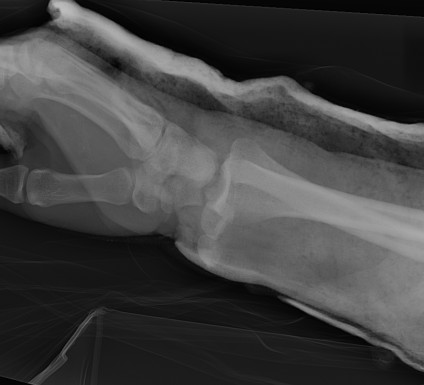

Dislocated Radiocarpal Joint Dislocated Radiocarpal Joint AP